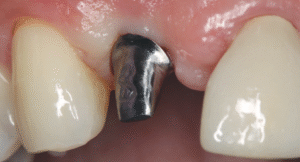

Titanium Teeth: The Gold Standard in Dental Implants

You’re thinking about getting a dental implant, and you’re wondering—what material should I choose? The good news is that titanium has been the answer for...